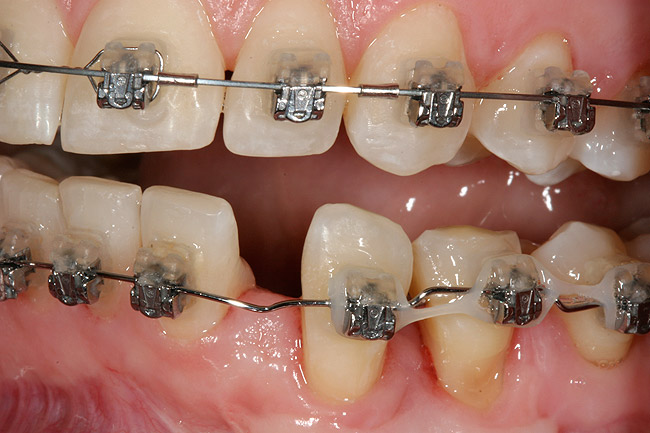

Figure 2  A preoperative retracted anterior view of the failing implant in the site of tooth No. 22.

Figure 2

A 28-year-old Caucasian female presented to the periodontist with a complaint of a mobile implant in the site of tooth No. 22 (Figure 2 and Figure 3). The patient had a congenitally missing tooth No. 23. No. 22 had erupted into site No. 23, leaving a vacancy at site No. 22, and was the reason for the original implant at site No. 22.

The patient had no medical concerns and had a history of an implant placement in December 2002 when she was 25 years old. In February 2005, she presented with a mobile implant and an associated advanced peri-implantitis. Radiographic review at the initial examination demonstrated significant destruction of the dentoalveolar ridge around the implant as well as around the adjacent natural dentition. Emergency-based treatment involved surgical implant removal only and debridement of the infection (Figure 4 and Figure 5). Following uneventful healing, an advanced ridge defect was apparent at the edentulous site and moderate and advanced attachment loss noted at No. 22D and No. 21M, respectively (Figure 6 and Figure 7). This case demonstrates bone loss of two separate origins: lack of bone because of tooth agenesis and destruction of bone from inflammatory peri-implantitis.